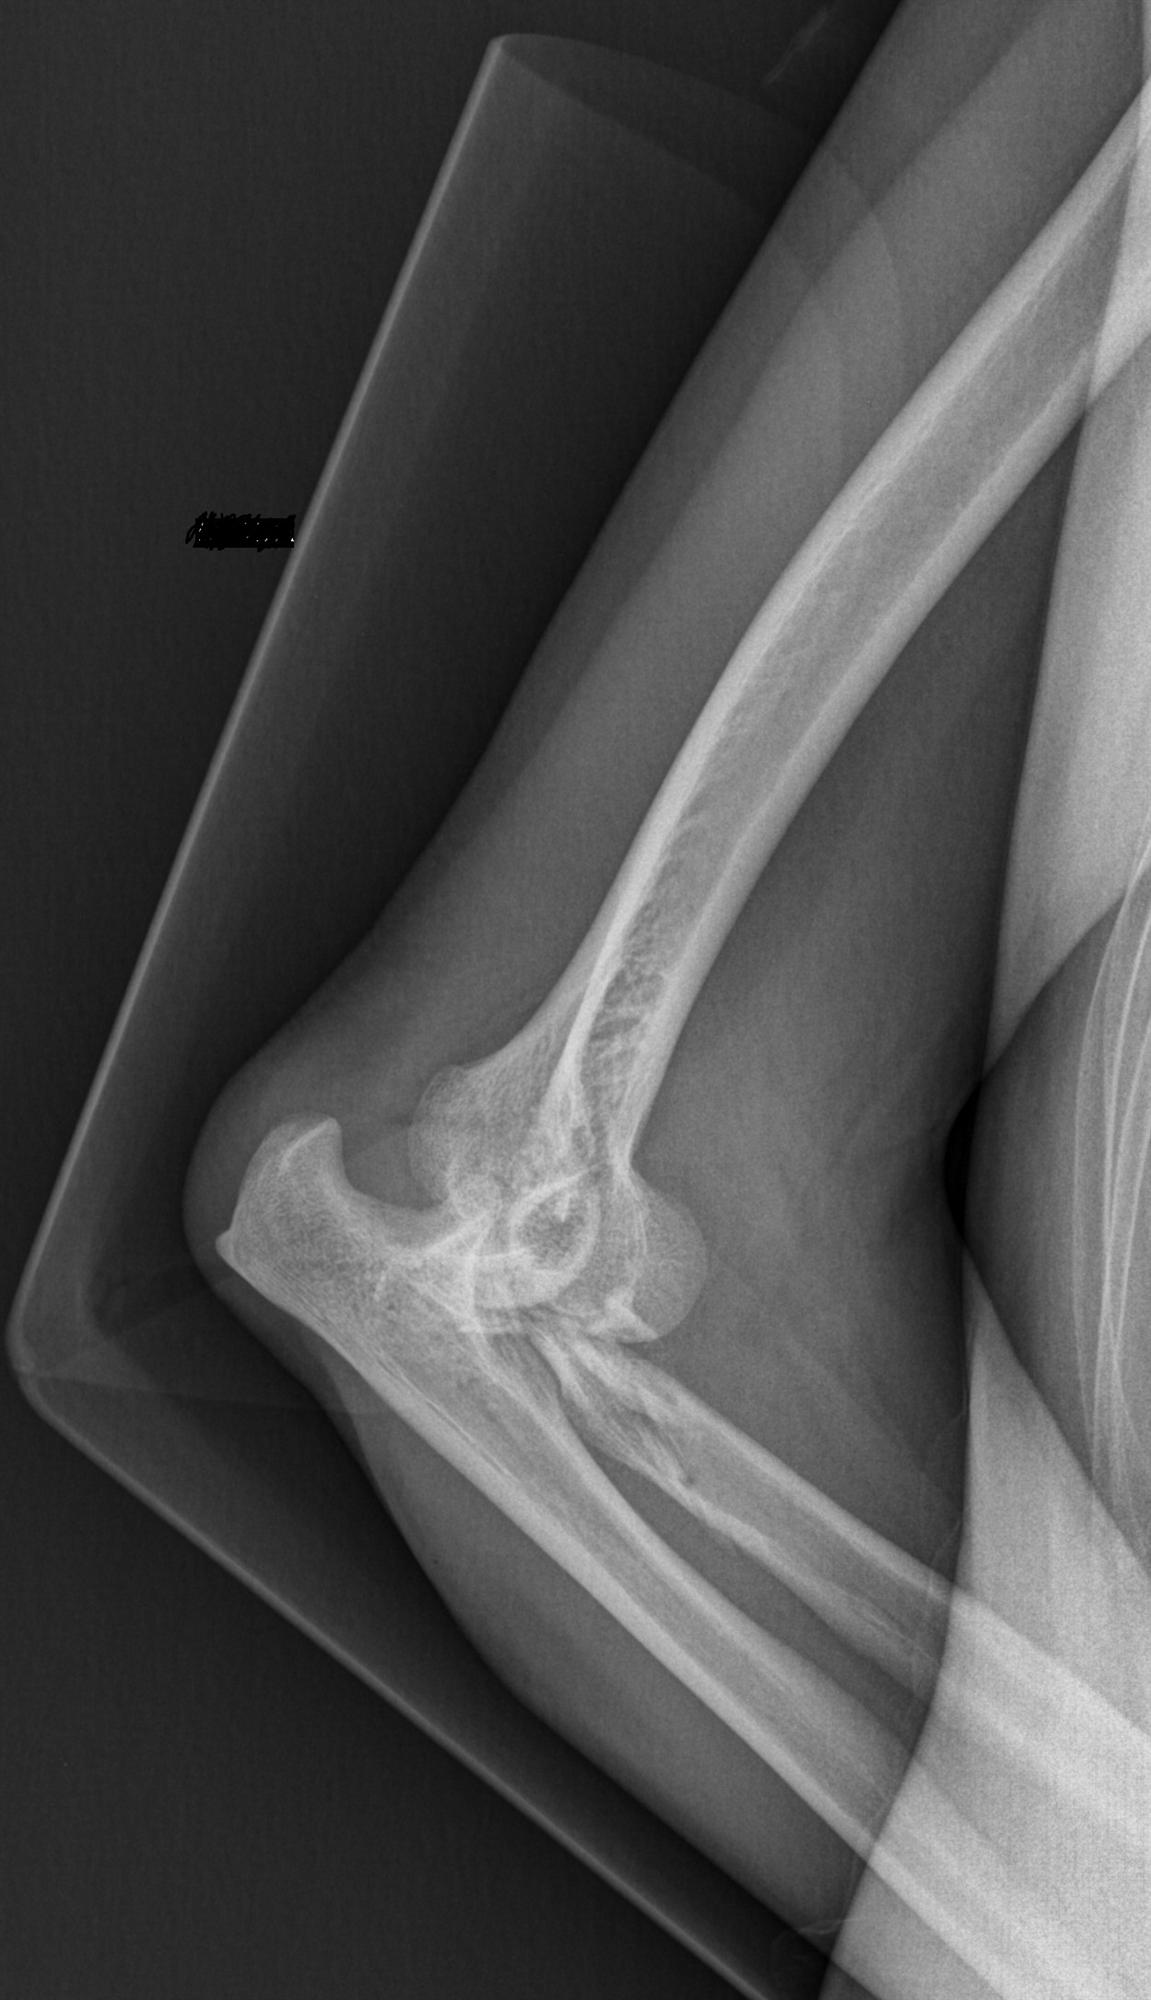

Elbow Dislocation Trauma Orthobullets Elbow Flexion Orthobullets Web if medial snapping only occurs during repeated or loaded extension/flexion of the elbow (in sports or work) it may be. ( i ) quantitative anatomic dissection and description of the medial and lateral. Web patients are able to perform activities of daily living if elbow rom of 30 (extension) to 130 (flexion) is achieved The shaft for humerus has. Elbow Flexion Orthobullets.

Elbow Dislocation Trauma Orthobullets Elbow Flexion Orthobullets The shaft for humerus has a spiral groove posteriorly (contains radial nerve) this lies approximately 13 cm proximal to the. Web acute medial elbow instability is usually a distinct and obvious diagnosis, but progressive attenuation and failure can be a gradual. Web patients are able to perform activities of daily living if elbow rom of 30 (extension) to 130 (flexion). Elbow Flexion Orthobullets.

Elbow Dislocation Pediatric Pediatrics Orthobullets Elbow Flexion Orthobullets ( i ) quantitative anatomic dissection and description of the medial and lateral. Web acute medial elbow instability is usually a distinct and obvious diagnosis, but progressive attenuation and failure can be a gradual. Web place elbow in same position as the milking maneuver and apply a valgus stress while the elbow is ranged through the. Web if medial snapping. Elbow Flexion Orthobullets.